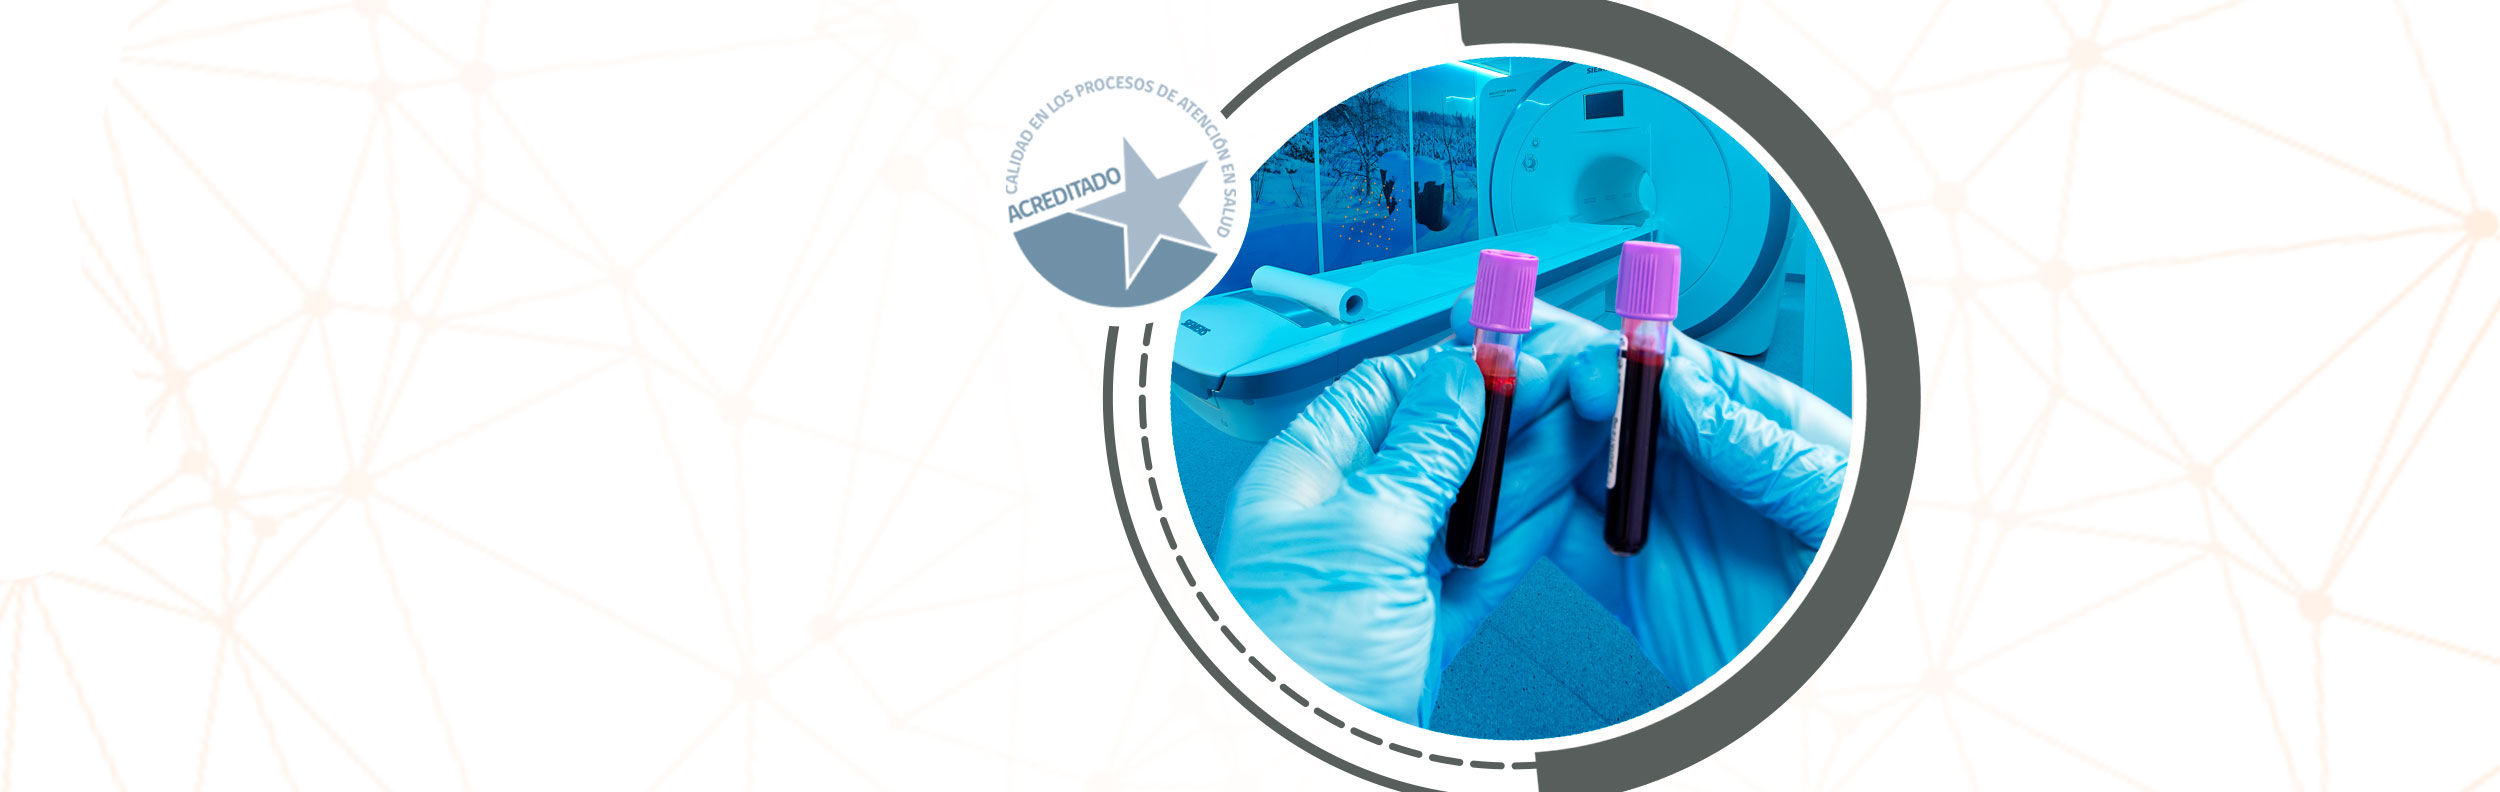

Nacemos en la ciudad de Rancagua como uno de los centros de imagenología más modernos de la región de O'Higgins. Ofrecemos una amplia gama de servicios de exámenes con tecnología de vanguardia, incluyendo TAC de 128 canales, Resonancia Magnética de 3 Teslas y PET-CT.

Nuestro compromiso con la mejora continua en la calidad de las imágenes y nuestra capacidad médico-técnica nos permite ofrecer diagnósticos más precisos, beneficiando tanto a médicos especialistas como a nuestros pacientes. Como referentes en diagnóstico médico, somos el único centro acreditado de la región en procesos de atención en salud en imagenología médica.

En 2024, para mejorar aún más nuestros servicios, hemos habilitado una nueva sala toma de muestras de laboratorio.